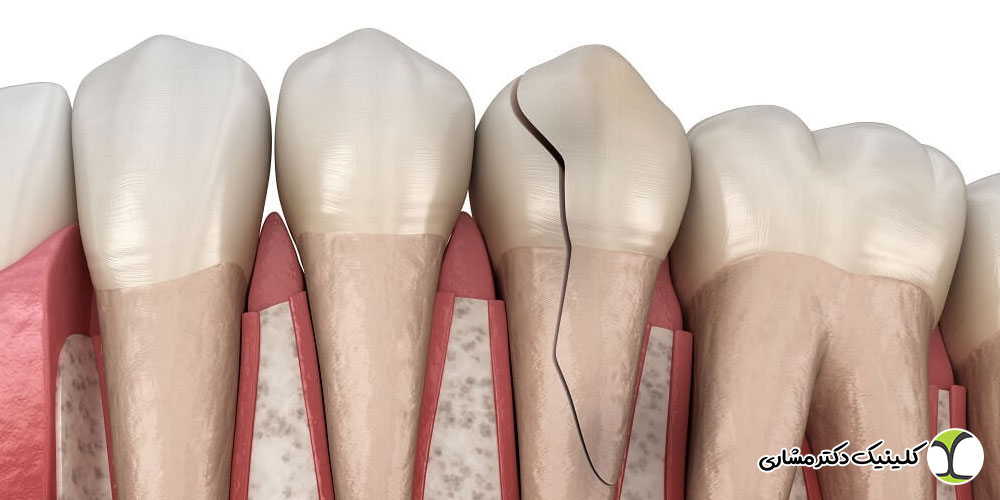

- ضربه و شکستگی

- ترکهای دندانی

پوسیدگی عمیق یا ترکهای دندانی

ترکهای دندانی نیز حتی اگر کوچک باشند، میتوانند باعث نفوذ باکتری ها به ریشه شوند. مناطقی که ترک دارند معمولاً درد هنگام جویدن یا درد هنگام سرما ایجاد میکنند.